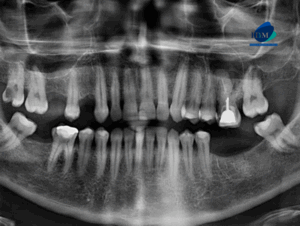

Paciente femenina acude a IDM- Sede Miraflores para evaluar la extracción de terceras molares. Radiografia Panorámica A la evaluación de la radiografía panorámica se observa